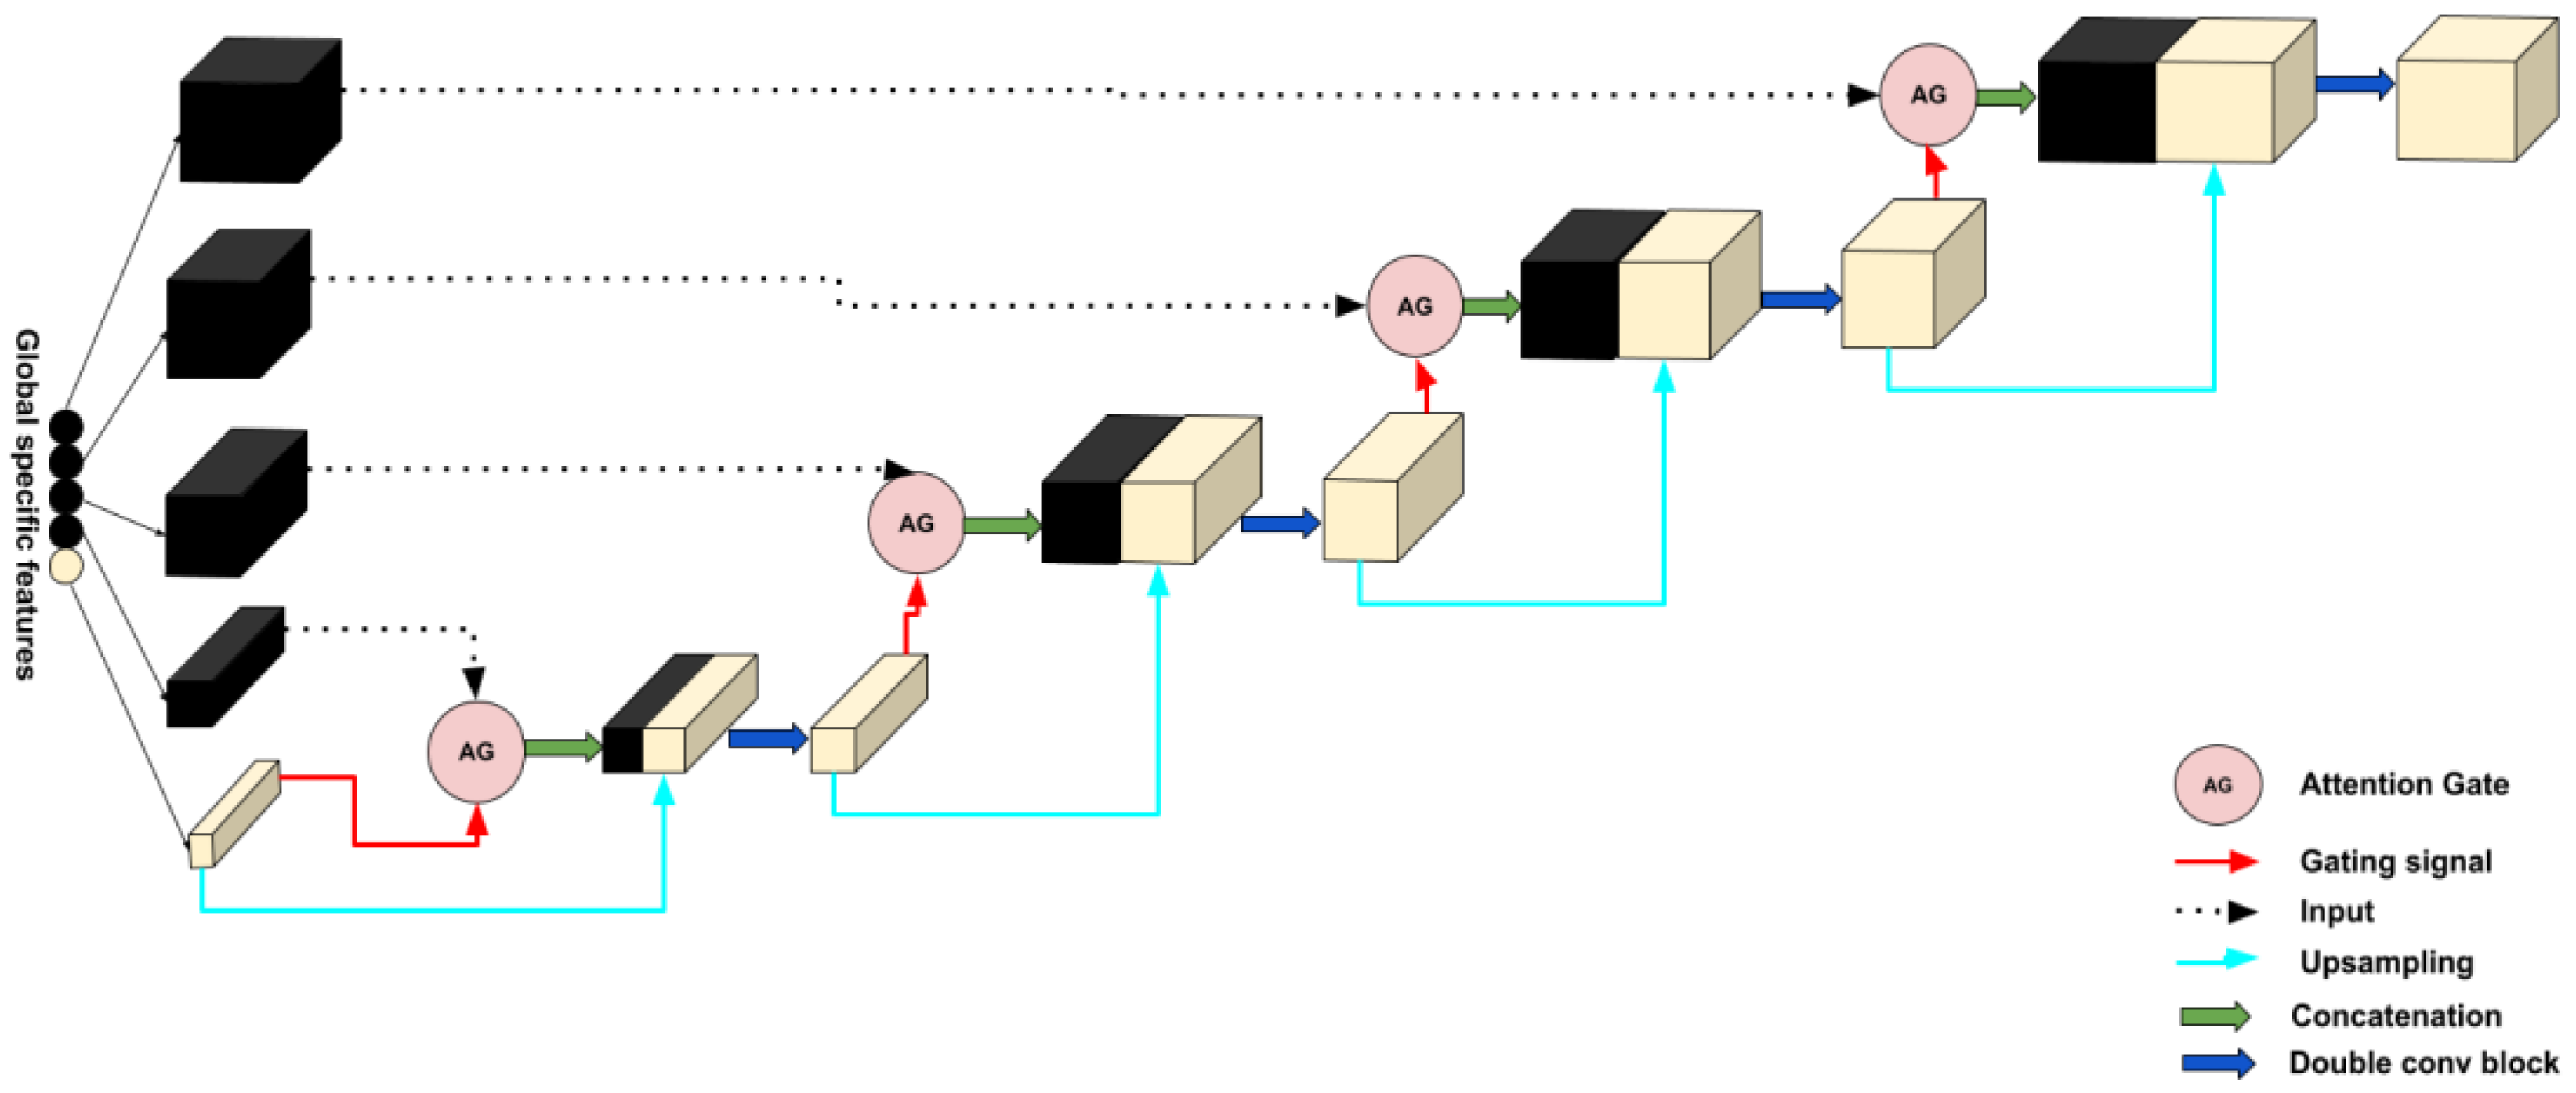

2.2.2. Decoder